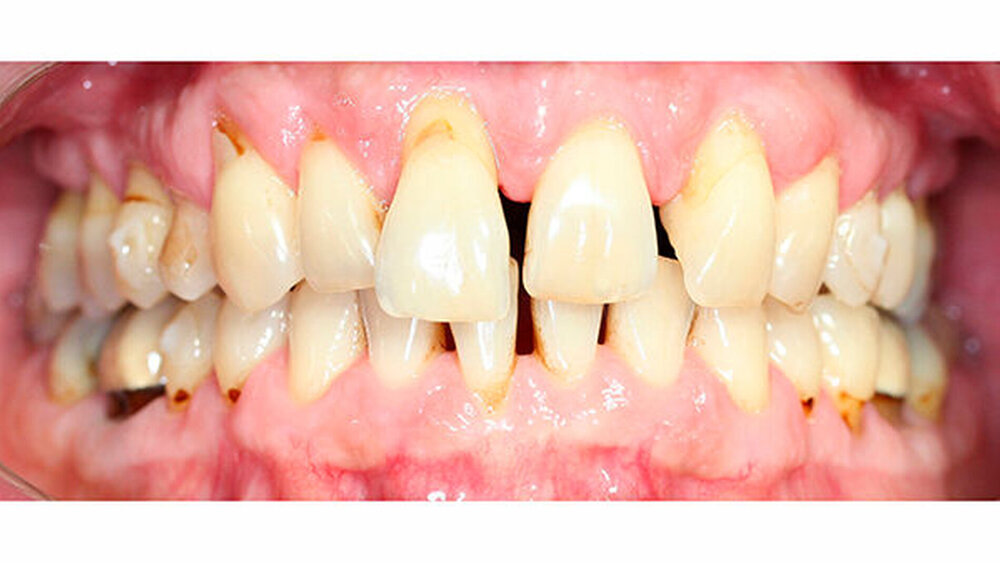

Intraoral zeigte sich ein bereits konservierend versorgtes permanentes Gebiss mit aktivem und inaktivem kariösen Geschehen. Große Anteile der Zahnhälse lagen nach Zahnfleischrückgang in Kombination mit Knocheneinbrüchen frei. Zahn 27 wurde bereits extrahiert.

Eine Beurteilung der parodontalen Situation an Zahn 11 offenbarte mesial und distal Sondierungstiefen von jeweils 6 mm.

Kieferorthopädisch imponierte beidseits eine neutrale Verzahnung bei einem tiefen Biss von 5 mm - bedingt durch die Verlängerung beider Frontzahngruppen. Besonders Zahn 11 zeigte eine erhebliche Verlängerung und Protrusion mit einer sagittalen Frontzahnstufe von 5 mm. Sowohl die Frontzähne im Ober- als auch im Unterkiefer wiesen eine lückige Beziehung zueinander auf (Abbildung 1).